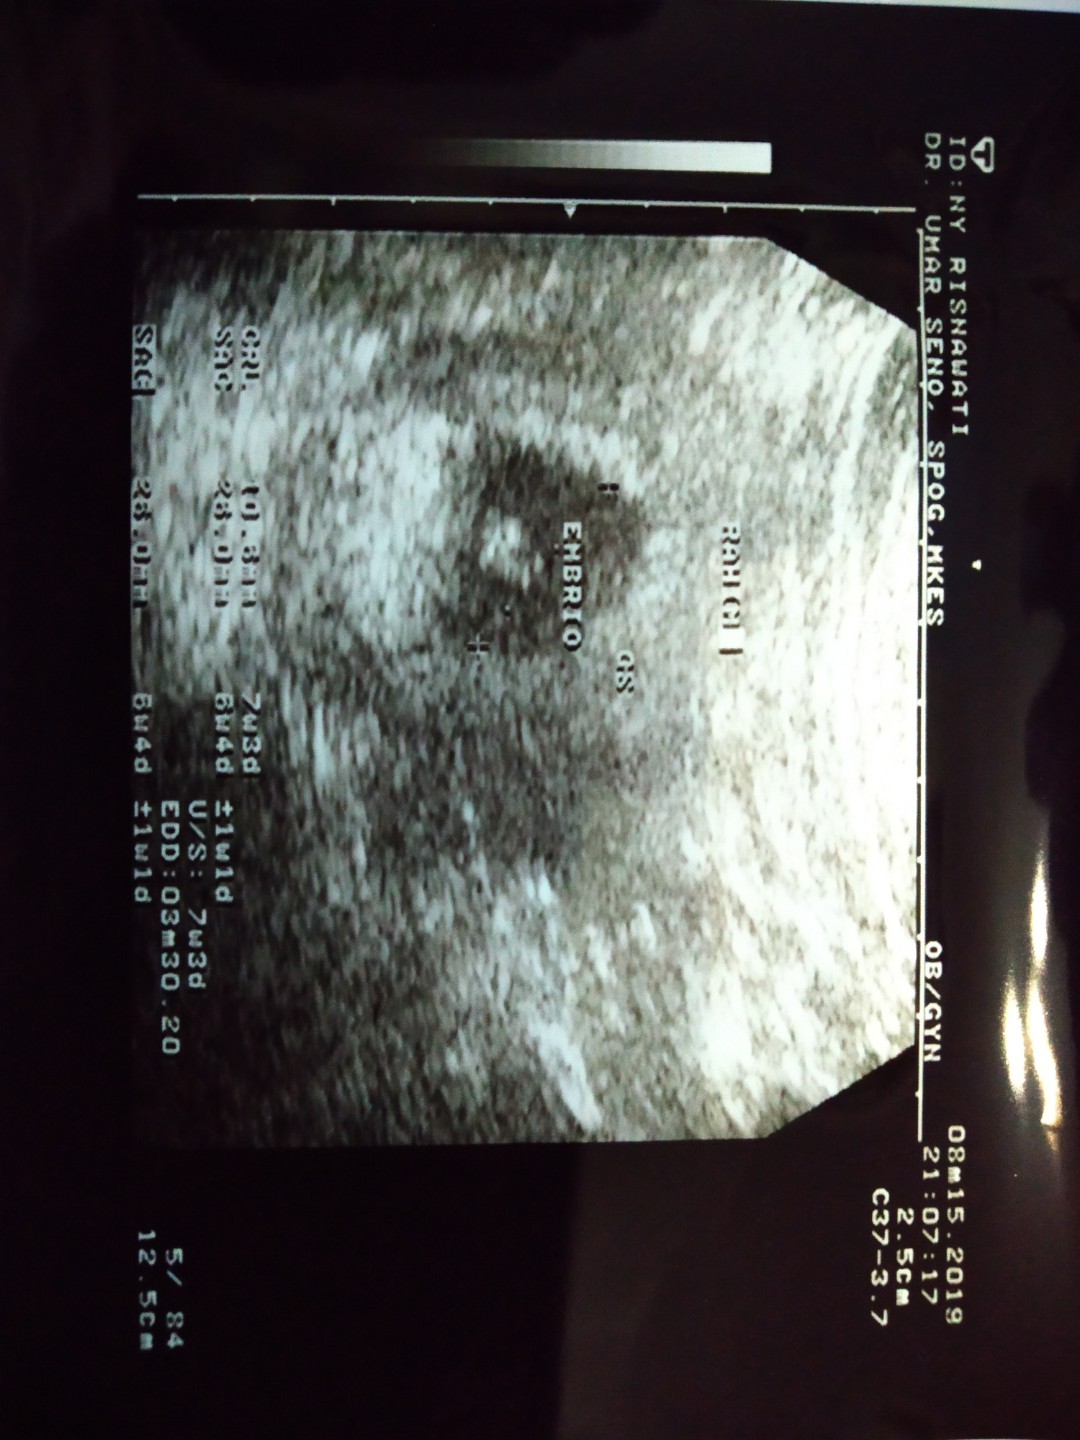

usg

Bun,usia 6w gambar usg nya kygini normal ga sih Bun?? Tadi dokternya bilang, ga berkembang masa?? Disuruh balik lagi seminggu selanjutnya untuk di usg lagi